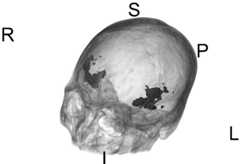

图10分割的侧裂3D展示。Figure 10 Sylvian fissure segmented in 3D.

(2)对称拟合生成:将正常侧侧裂以中轴线做镜像对称,拟合为病变侧侧裂(图9和10)。(2) Symmetrical fitting generation: the normal Sylvian fissure is mirror-symmetrical to the central axis, and fitted to the diseased Sylvian fissure (Figs. 9 and 10).